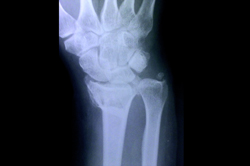

Lower Radius